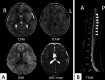

Myelin oligodendrocyte glycoprotein is a major target of the humoral immune response in children affected by inflammatory demyelinating diseases of the central nervous system. Although myelin oligodendrocyte glycoprotein causes autoimmune encephalitis in different animal models, the relevance of this mechanism in human autoimmune diseases of the central nervous system is unclear. We herein report a child with acute disseminated encephalomyelitis possibly triggered by central nervous system infection of primary herpes simplex virus in the presence of antimyelin oligodendrocyte glycoprotein antibody. A healthy 5-year-old Japanese boy suffered from acute disseminated encephalomyelitis. He was positive for antimyelin oligodendrocyte glycoprotein antibody in both the serum and the cerebrospinal fluid, and herpes simplex virus-1 DNA on polymerase chain reaction of the cerebrospinal fluid. We speculated that the central nervous system infection of primary herpes simplex virus disrupted the blood-brain barrier, and antimyelin oligodendrocyte glycoprotein antibody already present in serum was transferred to the cerebrospinal fluid, resulting in the onset of acute disseminated encephalomyelitis. This might be the mechanism underlying postinfectious acute disseminated encephalomyelitis associated with myelin oligodendrocyte glycoprotein antibody.